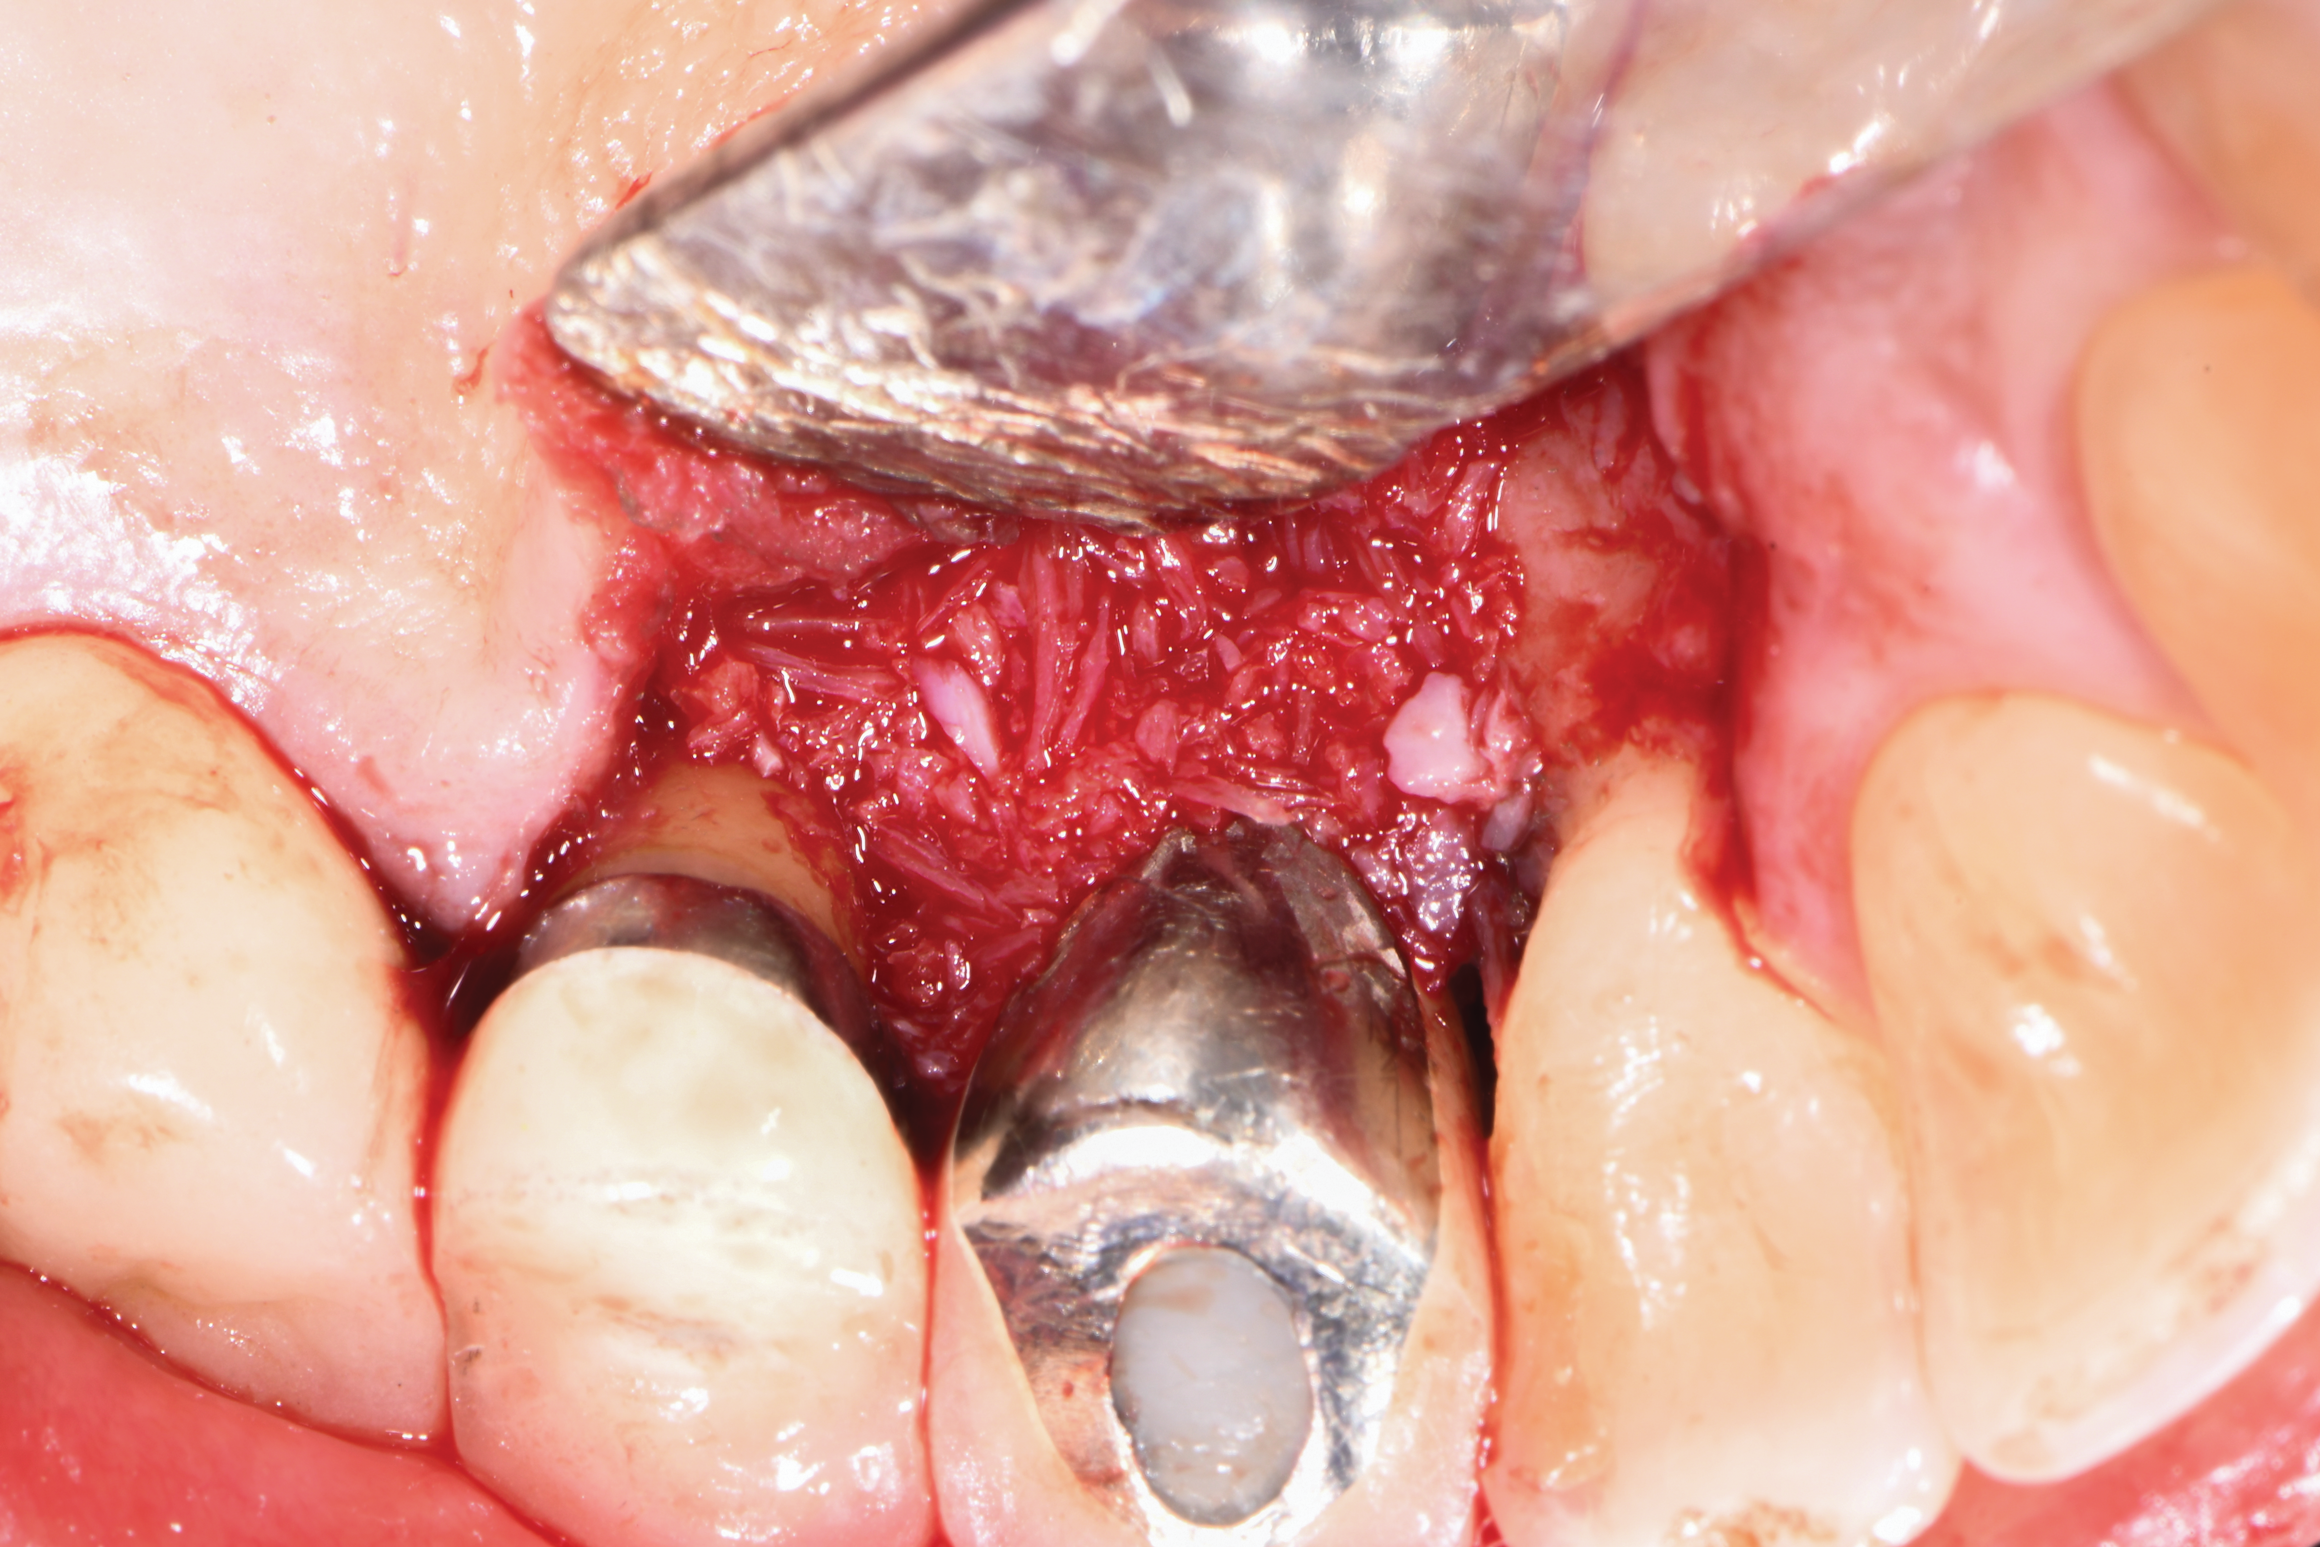

A surgical approach was planned that included implantoplasty and guided bone regeneration. After local anesthesia was administered, full-thickness flaps were elevated using an envelope flap on the buccal aspect and a triangular design on the palate to expose the defects. Removal of granulomatous tissue from the area enabled visualization of a narrow circumferential lesion on the facial (Figure 3) and a one- to two-wall combination defect on the palatal (Figure 4). The surface was initially treated with a 50% solution of citric acid for 30 seconds followed by thorough rinsing with sterile saline. This was followed by implantoplasty using a 30-fluted finishing bur of surgical length. Because the implant was very narrow, achieving a matte-like surface was not possible; thus, the goal was to reduce the threads and lightly remove the implant's outer surface to expose fresh titanium (Figure 5 and Figure 6). The modified surface was treated again with citric acid and rinsed with sterile saline.

Fig 5. Buccal view after implantoplasty was performed.

Figure 5

Fig 6. Palatal view following implantoplasty demonstrating reduction of the threads and surface modification.

Figure 6